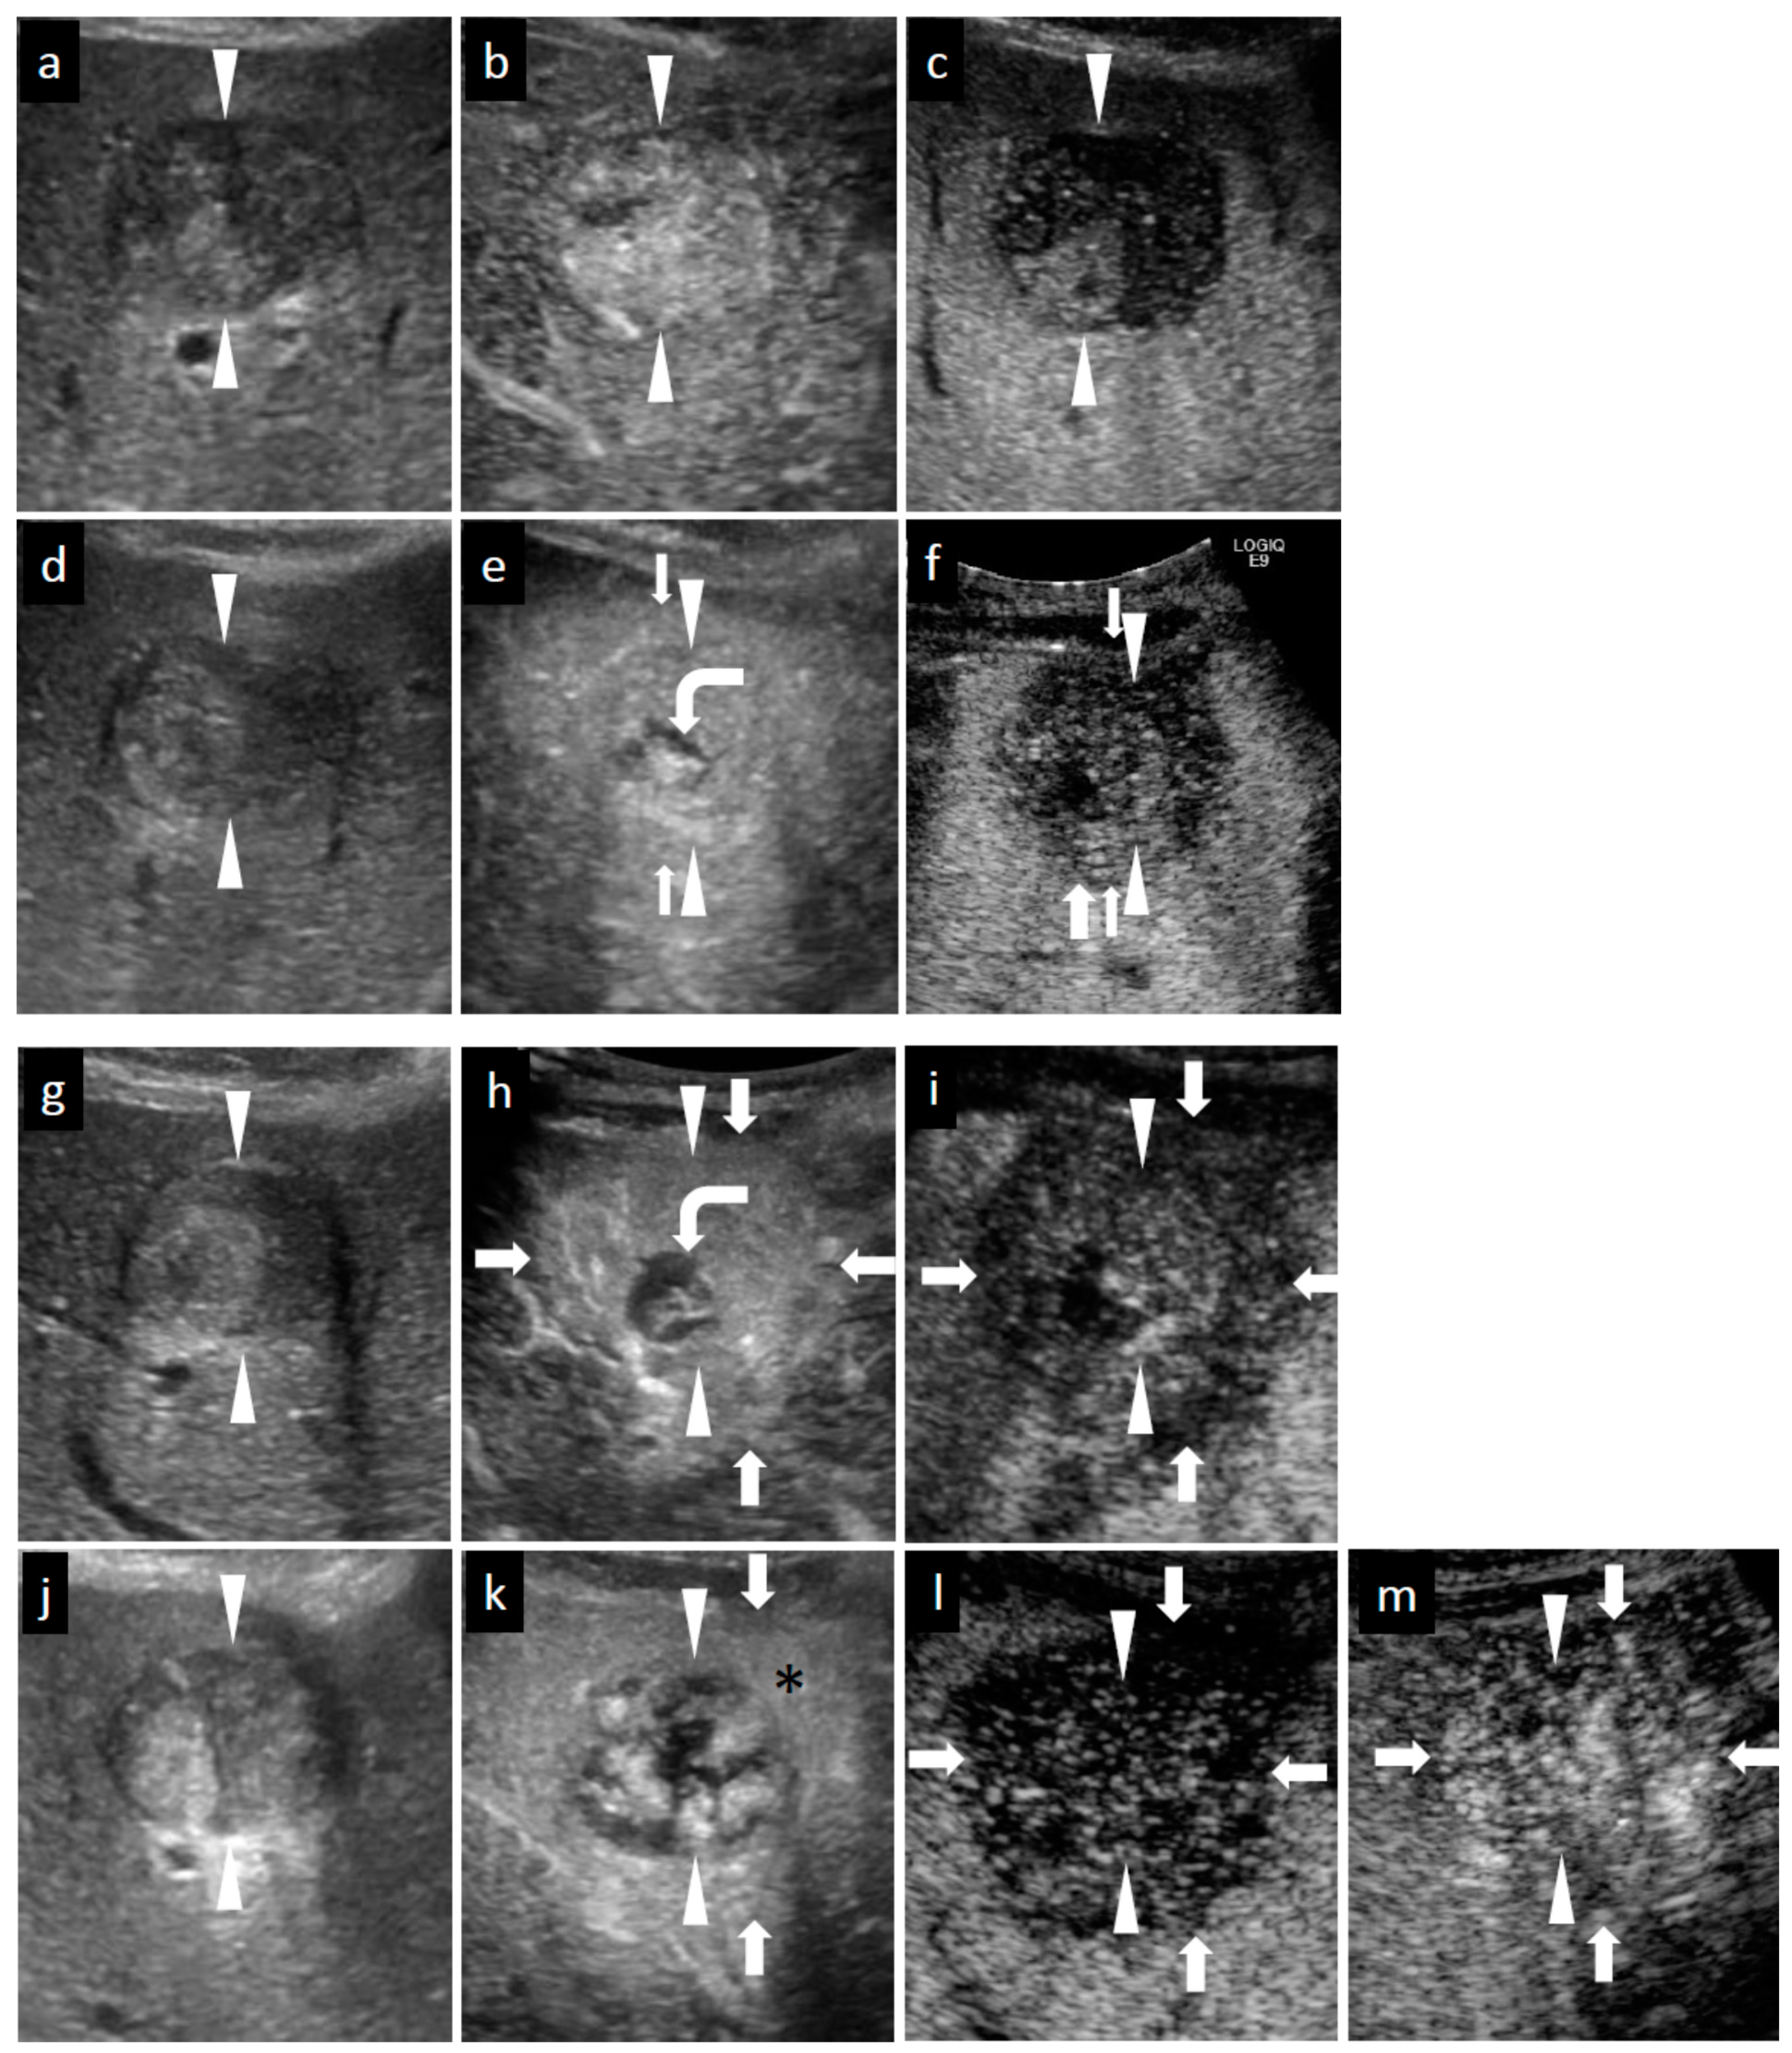

Figure 3.

Grayscale ultrasound (US) and contrast-enhanced US with Sonazoid (SCEUS) images before and after radiotherapy (RT) for an HCC lesion (maximum diameter: 34 mm) in segment III/IV, evaluated as residue after RT. RT was selected as treatment because the lesion was located adjacent to the left portal vein and the tumor size was more than 3 cm (as the maximum diameter). Hypofractionated radiotherapy was performed as the bowel organ was adjacent to the lesion. Before RT (a–c): A hyperechoic lesion was observed using grayscale US (a). This lesion showed hypervascularity during arterial phase (AP) SCEUS (b) and hypoechoic (perfusion defect) during the post-vascular phase (PVP) (c). One month after RT (d–f): The tumor size did not change on grayscale US (d). Using SCEUS, the HCC lesion showed hypervascularity with a partially hypovascular area (curved arrow) during the AP (e) and was hypoechoic during the PVP (f). The surrounding liver parenchyma showed slight hypervascularity during the AP (e) and was hypoechoic during the PVP (f). Four months after RT (g–i): The tumor size did not change on grayscale US (g). Using SCEUS, the HCC lesion showed hypervascularity with a partially hypovascular area (curved arrow) during the AP (h). The surrounding liver parenchyma showed apparent hypervascularity during the AP (h). Both the HCC lesion and the surrounding liver parenchyma appeared as a perfusion defect during the PVP (i). Thirteen months after RT (j–m): The tumor size did not change on grayscale US (j). Using SCEUS, compared with 4 months after RT, the HCC lesion showed hypervascularity during the AP (k). AP SCEUS showed slight hypervascularity of the surrounding liver parenchyma (k). Both the HCC lesion and the surrounding liver parenchyma appeared as a perfusion defect during the PVP (l). The boundary between the HCC and the surrounding liver parenchyma was unclear (l). After re-injection of Sonazoid during the PVP, both the HCC and the surrounding liver parenchyma showed hypervascularity (m). In this case, tumor size reduction and the disappearance of tumor vascularity were not observed during 13 months follow-up. Arrowheads indicate the margins of the HCC lesion. Arrows show the margins of the irradiated surrounding liver parenchyma. Pathological findings obtained from irradiated HCC area (n–p), irradiated surrounding non-tumor area (q,r), and non-irradiated non-tumor area (s,t) at 13 months after RT. For the irradiated HCC area, hematoxylin and eosin (HE) staining showed obvious cell atypia. Specifically, hypercellularity and larger, irregularly shaped nuclei can be seen. The nuclear cytoplasmic ratio is significantly higher. A few multinucleated giant cancer cells can be seen (n). Silver staining showed that reticular fibers have totally disappeared, resulting in poorly differentiated HCC (o). CD34 staining showed strong diffuse expression of CD34, suggesting increased neovascularization resulting from sinusoidal capillarization and the formation of sinusoid vascular endothelium in HCC (p). Irradiated surrounding non-tumor area showing hypervascularity during arterial phase SCEUS (* mark seen in (k)): HE staining showed neither cancer cells nor hepatocytes. Infiltration of inflammation cells (†) and severe fibrosis (‡) are noted (q). CD34 staining showed diffuse expression of CD34 in infiltration of inflammation cells (†) and severe fibrosis regions (‡) (r). Non-irradiated non-tumor area: HE staining showed normal hepatocytes with the normal nucleus shape and the nuclear cytoplasmic ratio. Thin trabeculae are clearly visualized (s). The negative expression of CD34 is seen (t).